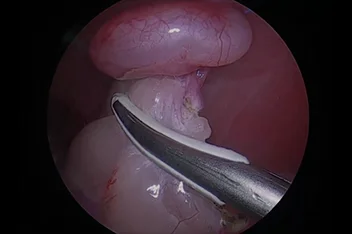

관절경

개,고양이 들은 다양한 관절질환이 존재하고, 복합적으로 존재하는 경우도 빈번합니다.

정확한 진단이 나지 않은 뒤 수술을 하게되면 증상개선이 더디거나 개선이 안될 수 있어, 정확한 진단이 필요합니다.

관절의 경우 X-ray 촬영등으로 진단의 한계가 명확하며, 상위 검사인 CT, MRI 촬영으로도 진단의 한계가 있습니다.

이때 관절경은 내부 구조물들을 직접 시각화 하여 보다 정확한 관절의 상태를 확인하고 진단할 수 있으며, 진단과 치료를 동시에 진행하는 경우도 있습니다. 대표적으로 십자인대단열(CCLR), 골연골염(OCD), 자뼈꿈치돌치유합부전(UAP), 내측관상돌기질환(MCD) 등에 활용될 수있습니다.

관절경 팔꿈치관절(Elbow) 확인

관절경 무릎관절(Stifle) 확인 (반월판 및 십자인대)